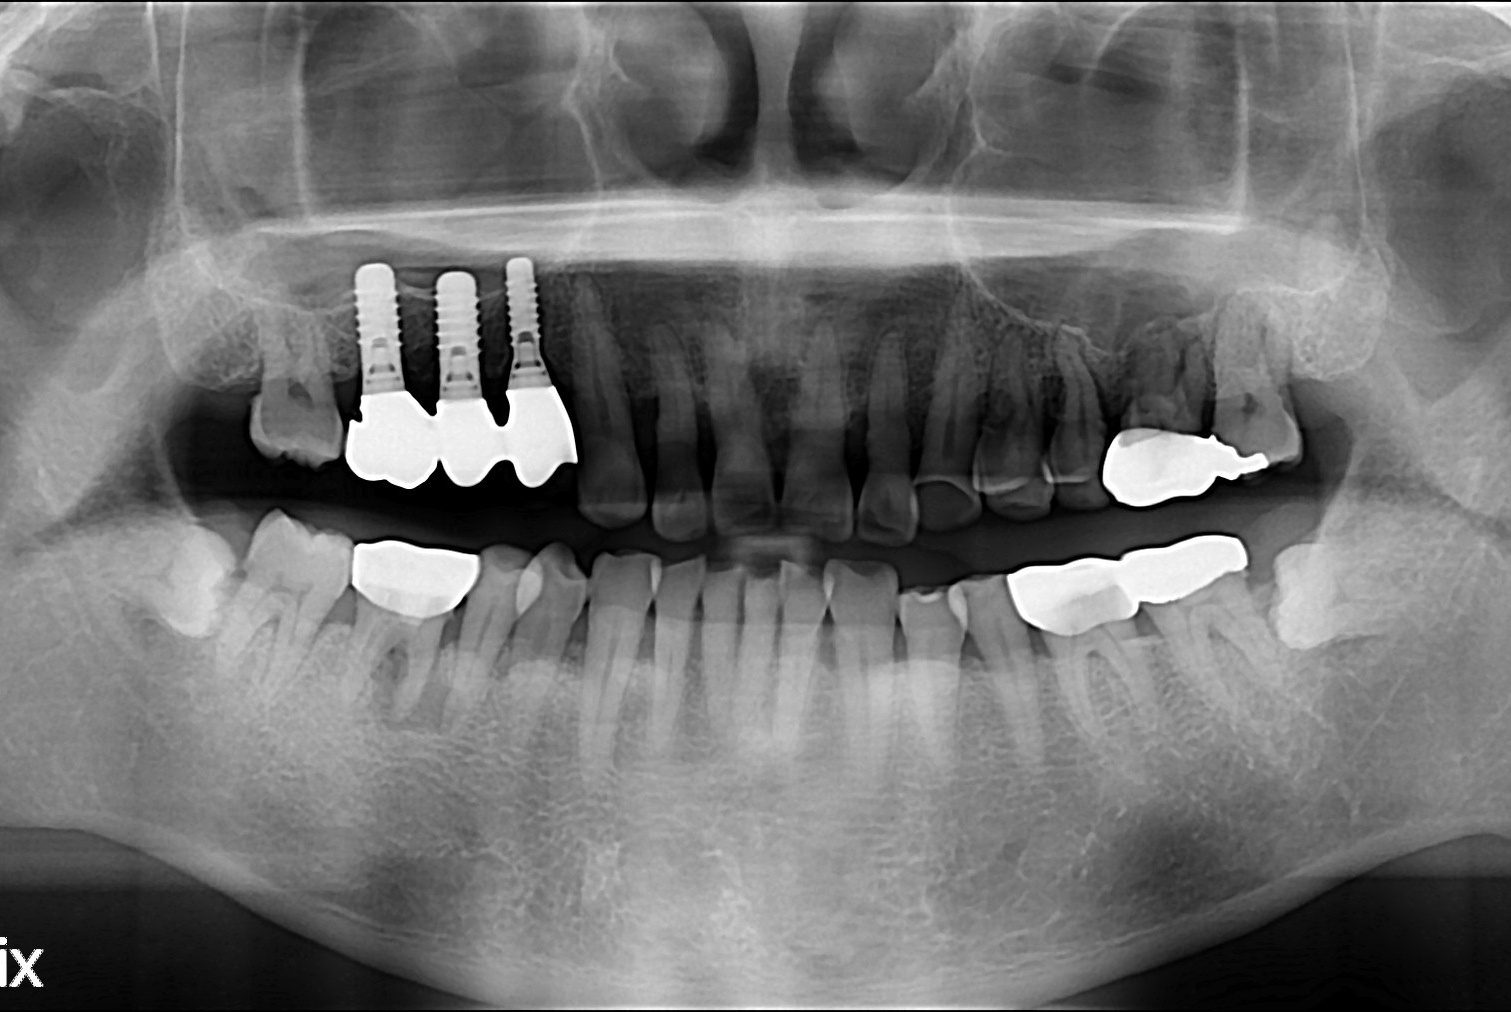

치료전 : 2018-05-09

치료후 : 2018-06-22

세종치과는 많은 환자와 다양한 케이스를 바탕으로 항상 편안한 임플란트 수술을 제공하고자 노력하고,

오래동안 튼튼히 쓸 수 있는 임플란트 수술을 가장 큰 목표로 삼고 있습니다